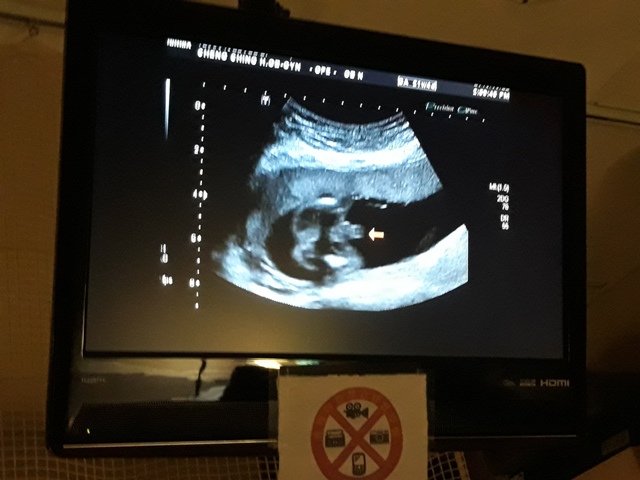

早上和小純去林婦產科看診,今天最主要是要確認有沒有懷孕,過年那段期間,小純跟我說他MC一直都沒來,而且很想吐,用驗孕棒驗的結果,都是懷孕。我第一次去林婦產科,他是一家蠻大間的診所,裡頭有許多孕婦等著看診。

當小純進入診間看診時,我並沒有進去,因為小純說,有時男生不能進去,會被請出來。在外頭等待的我感到很緊張,不久之後,謢理人員請我進入診間,我嚇了一跳,想說發生什麼事了,進入之後,得知小純真的懷孕了,而且已懷了九星期又五天。看診的醫師說,驗孕棒第二條線淡淡的,沒想到胚胎照出來那麼大了,說Baby很健康。還說一閃一閃的是他的心跳,有頭、有手、有腳還有臍帶。小純後來說看了內心覺得很感動,才叫我一起進去看。

小純肚子裡的Baby超音波圖↓